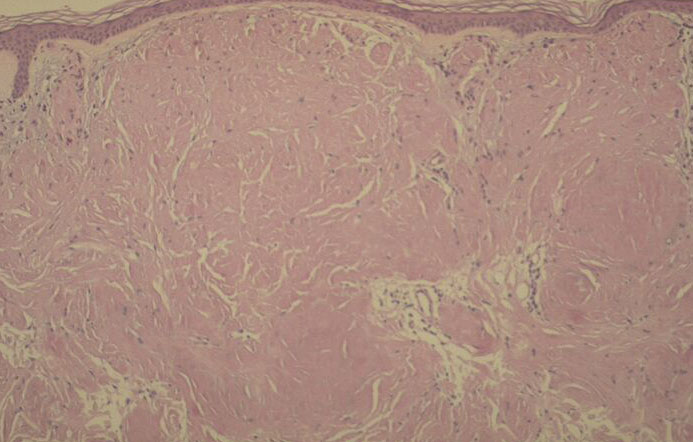

Nodular amyloid =الداء النشواني العقيدي